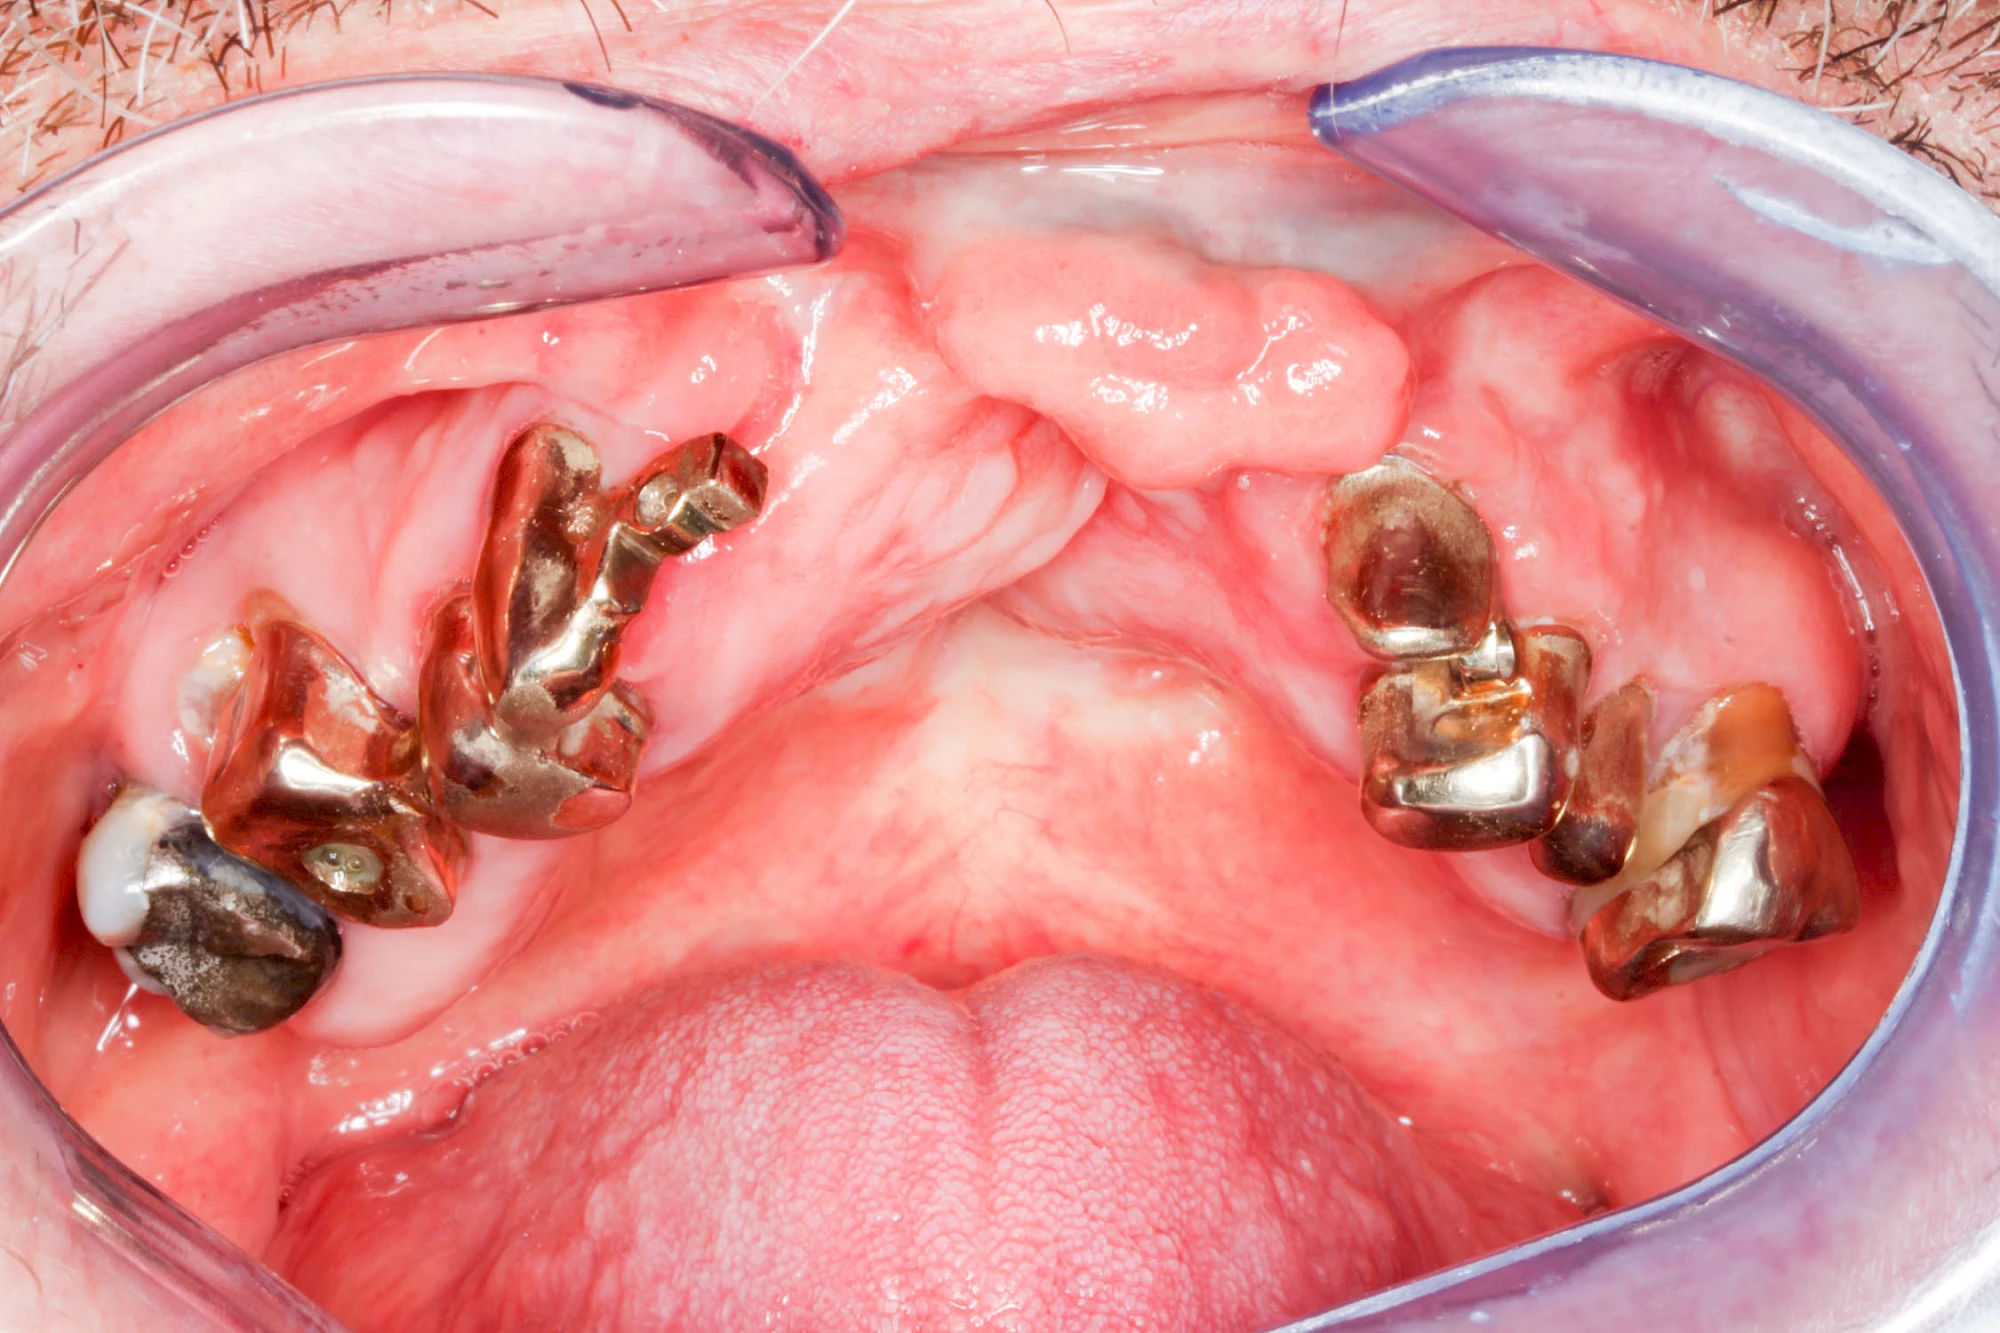

Knochenschwund (Atrophie)

Gehen die Zähne verloren, baut häufig auch der Kieferknochen ab (Knochenschwund). Die Geschwindigkeit und das Ausmaß des Knochenschwundes ist von vielen Faktoren abhängig. Neben der genetischen Veranlagung spielen auch Überbelastungen in Folge, z. B. bei ständigem Knirschen oder Pressen, eine Rolle. Auch wenn Zahnprothesen Tag und Nacht getragen werden, kann die ständige Belastung der Schleimhäute und des Knochens den Knochenschwund beschleunigen.

In seltenen Fällen schwindet nur der Knochen, aber nicht die bedeckenden Schleimhäute. In diesen Fällen spricht man von einem sogenannten "Schlotterkamm".